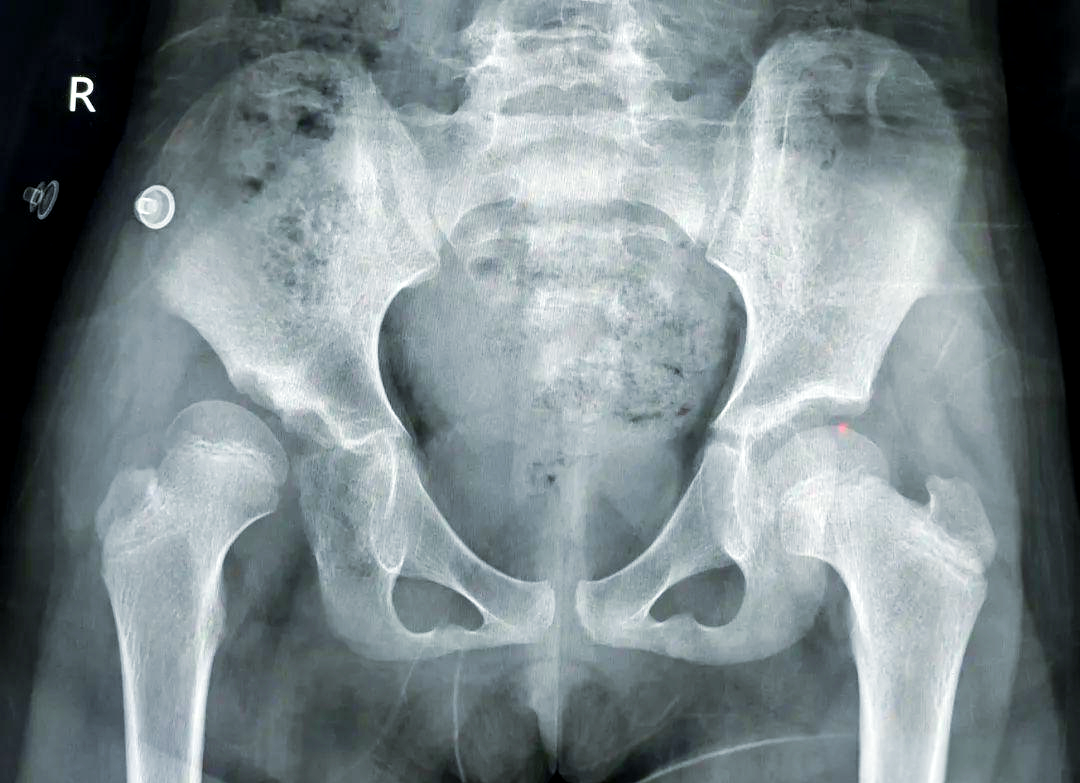

喜讯 矫形骨科专家秦泗河12月13号来合肥会诊手术 我国著名矫形骨科专家、秦泗河教授,将于2025年12月13日,到安徽合肥东南外科医院会诊手术! 马蹄内翻足 发育性髋关节脱位 学科带头人介绍 卢成 骨科主任 从事骨科临床工作二十多年,曾于2011年在清华大学附属医院师从中国著名矫形外科专家秦泗河教授学习矫形外科,积累了大量的临床诊疗经验。熟悉骨科常见病、多发病的诊断及治疗,在四肢畸形矫正及骨外固定技术领域有较深的造诣。 擅长:骨外固定及Iizarov技术治疗各种下肢畸形包括脊髓灰质炎后遗症、脑瘫肢体功能障碍、先天性髋关节脱位、膝内、外翻、先天性多发性关节挛缩症、骨缺损、骨不连、骨髓炎,以及先天性马蹄内翻足、拇外翻等各种复杂的足踝部畸形、脊柱裂后遗各种下肢畸形等。同时在成骨性肿瘤、成软骨性肿瘤、骨肉瘤等骨肿瘤疾病的治疗,股骨头坏死、颈椎病/腰椎病的手术治疗、椎体成形术、关节创伤、关节置换等方面也有颇深的造诣。 欢迎安徽省及周边地区患友积极就诊、复查。凡在安徽合肥东南外科医院就医患友,均由秦教授亲诊手术。 如您身边有先天性肢体畸形、儿麻、脑瘫等肢体运动功能障碍的患者,请不要错过与矫形大师面对面的交流和治疗机会。 联系人:卢成主任 电话:13855184363